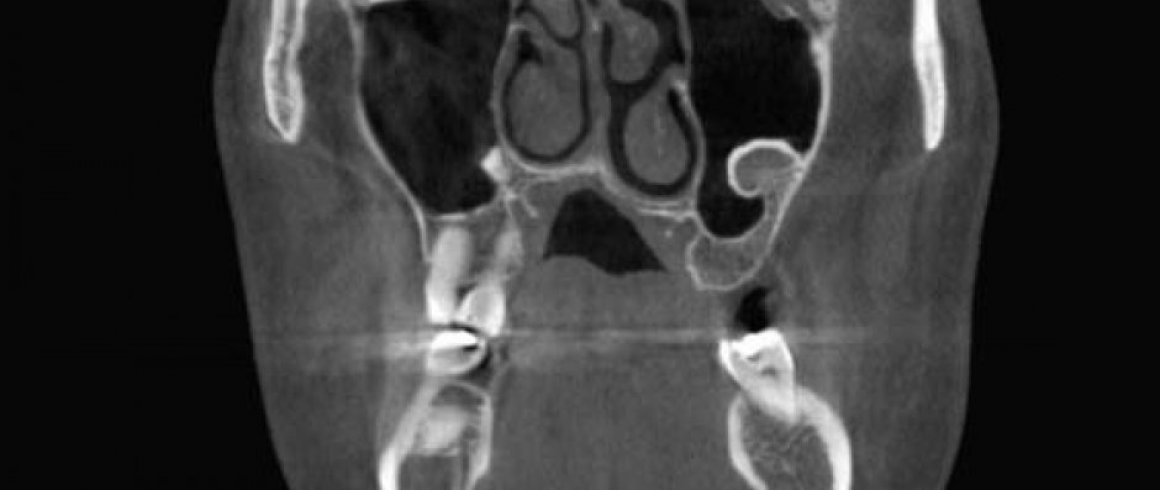

- Tomografía

- Implantes

- Localización de Diente Impactado

- Área Patológica